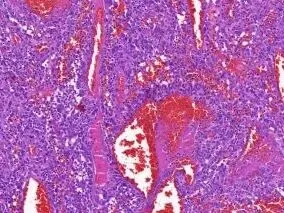

角化过度,表皮增生肥厚,皮突延长,肿瘤位于真皮内,排列较紊乱,肿瘤中央可见出血性裂隙,真皮乳头部可见无浸润带。

①肿瘤组织内有不规则的类似于血管腔的出血性裂隙。

②肿瘤附近的实体区域,尤其是细胞,常表现为良性纤维组织细胞瘤。

③细胞内外含铁血黄素的沉积。